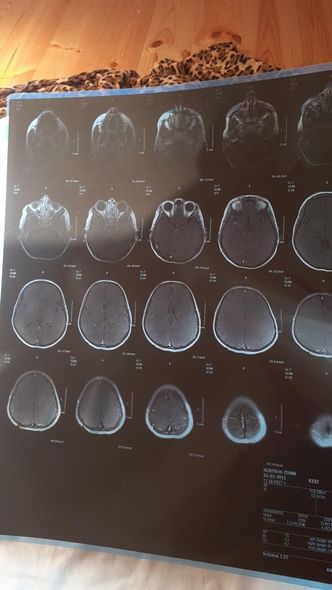

O qeyd edib ki, övladı Zəhra Hüccət qızı Nuriyeva həm autizmdən, həm də serebral iflicdən əziyyət çəkir:

“Biz Lənkəranda yaşayırıq. Beş övladım var. Onlardan ən böyüyü Zəhradır. Onun iki ağır xəstəliklə mübarizəsi, həqiqətən, bir ana olaraq məni məhv edir. Qızımın vəziyyəti günü-gündən ağırlaşır. Bir neçə ay öncə xeyirxah insanların dəstəyi ilə övladımı müalicə etdirməyə başlasaq da maddi vəziyyətimizə görə müalicə yenidən yarımçıq qalıb. Zəhranın gün ərzində 3-4 dəfə epilepsiyası tutur. Hər dəfə onu geri qaytara bilməyəcəyəm deyə qorxudan az qalıram dəli olam. Yardımsevər şəxslərdən mənim övladıma yenidən dəstək olmalarını, onun əlindən tutmalarını xahiş edirəm. Müalicə üçün hazırda 1 000 manata ehtiyacımız var”.